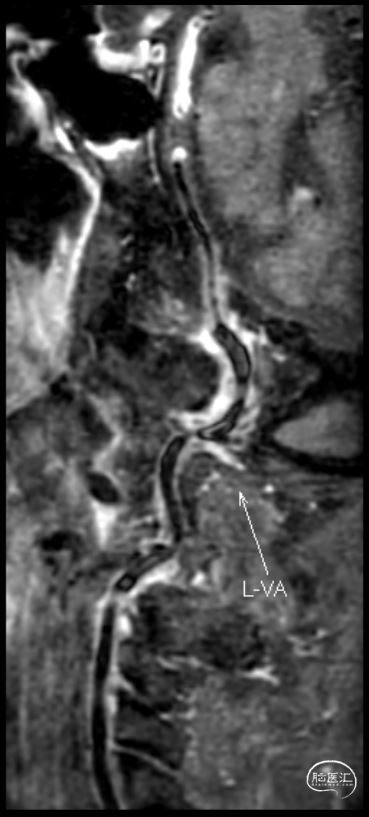

➢2023年11月14日

头颅MRI平扫+HRMRI:脑桥、中脑急性/亚急性脑梗死;双侧桥臂变性。

HRMRI:基底动脉闭塞并斑块合并局部出血;左侧大脑后动脉P1段斑块形成,相应管腔闭塞,左侧椎动脉V2-V4段斑块形成,相应管腔中重度狭窄,左侧椎动脉V4段管壁弥漫性增厚,相应管腔中度狭窄;右侧大脑后动脉纤细。

因右侧椎动脉颅内段血管狭窄,选取左侧椎动脉入路。左侧椎动脉开口迂曲,6F 导引导管放置于左侧椎动脉V2段。